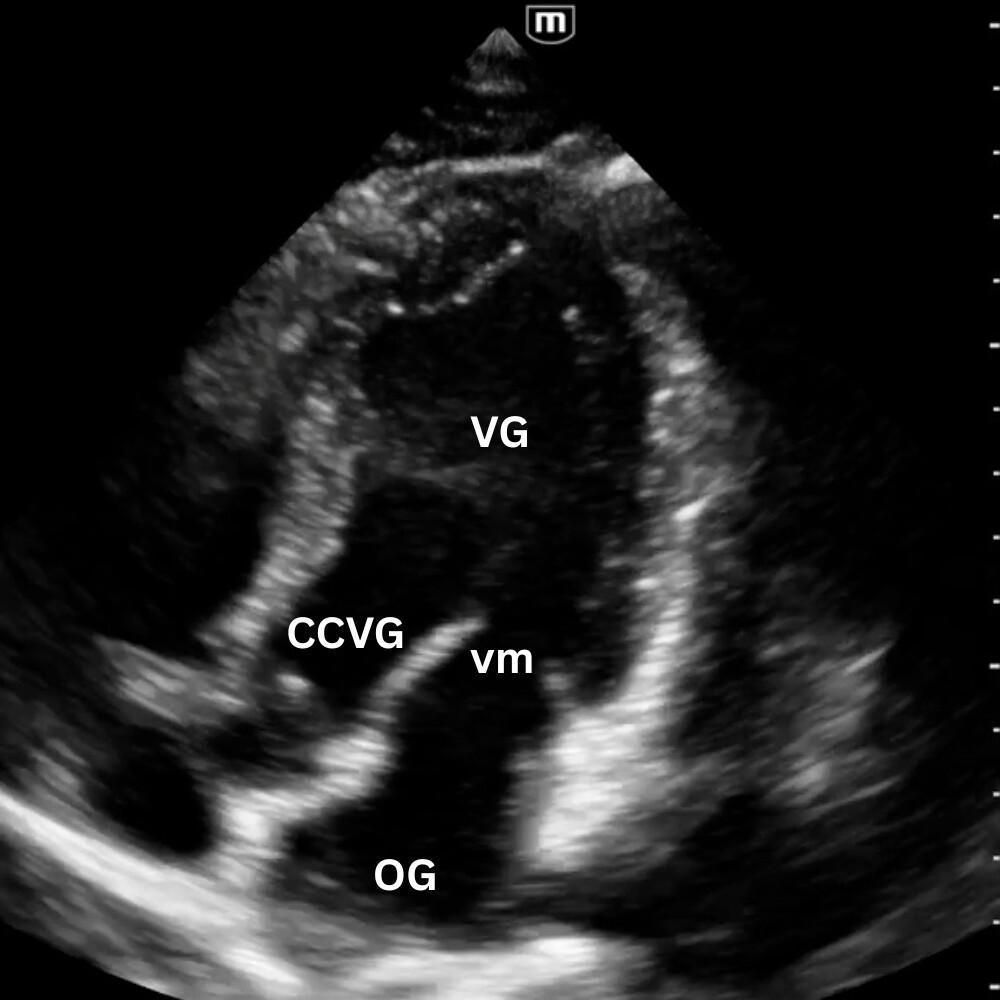

🔹 Vue Parasternale Grand Axe

Sonde au 3ᵉ–4ᵉ espace intercostal gauche, bord sternal, marqueur vers l’épaule droite.

Montre le VG, le VD antérieur, l’oreillette gauche, la valve mitrale, la valve aortique et la racine de l’aorte.

On y évalue :

- la contractilité du VG ;

- la présence d’un épanchement péricardique postérieur ;

- l’aspect de la racine aortique (dilatée, disséquée, hyperéchogène) et la mesure de la chambre de chasse du VG.